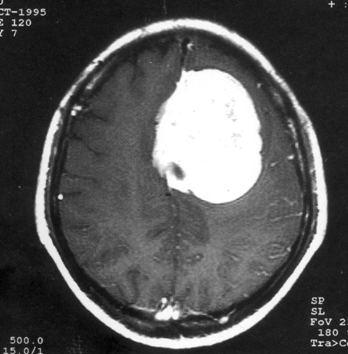

问题 病历摘要:??患者,男,40岁。发作性左下肢抽搐1年余,每次发作3~5分,每周发作1~2次。每次发作后感左下肢乏力,约半日后可自行恢复。既往身体健康。体检:神清,头顶部偏右有局限性骨性隆起(1.5×1.5cm),左鼻唇沟稍浅,伸舌居中。感觉、运动无明显异常。左浅反射减退,左下肢腱反射稍亢进,左Babinski征(-)。 根据病史、MR结果,考虑哪种诊断?提示:头颅?MR检查(见图)

选项 A.右顶叶星形细胞瘤 B.右顶叶转移瘤 C.脑膜瘤 D.右顶叶淋巴瘤 E.右顶叶少枝胶质细胞瘤 F.脑脓肿 G.右顶叶炎性肉芽肿

答案 C